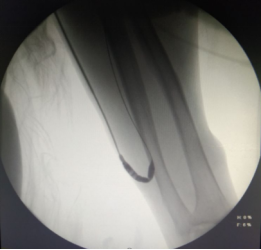

DSA下行血管造影+上腔静脉穿刺+置入长期透析导管手术过程(白色粗箭头所指用经皮血管穿刺套件进行上腔静脉穿刺过程)

02.上腔静脉穿刺长期透析导管置入术

邓某某 女 53岁,右侧肿胀手综合征,尿毒症,2-型糖尿病,长期使用自体动静脉内瘘透析,检查提示右锁骨下静脉、右无名静脉闭塞。由于患者血管闭塞时间长,病变累及两条血管,无法开通血管。

血液净化中心医生制定了内瘘结扎方案,把人为建立血流回心的“高速公路”封堵,DSA引导下穿刺上腔静脉置入一根23cm的长期透析导管,手术难度很大。